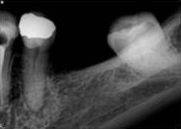

antes depois